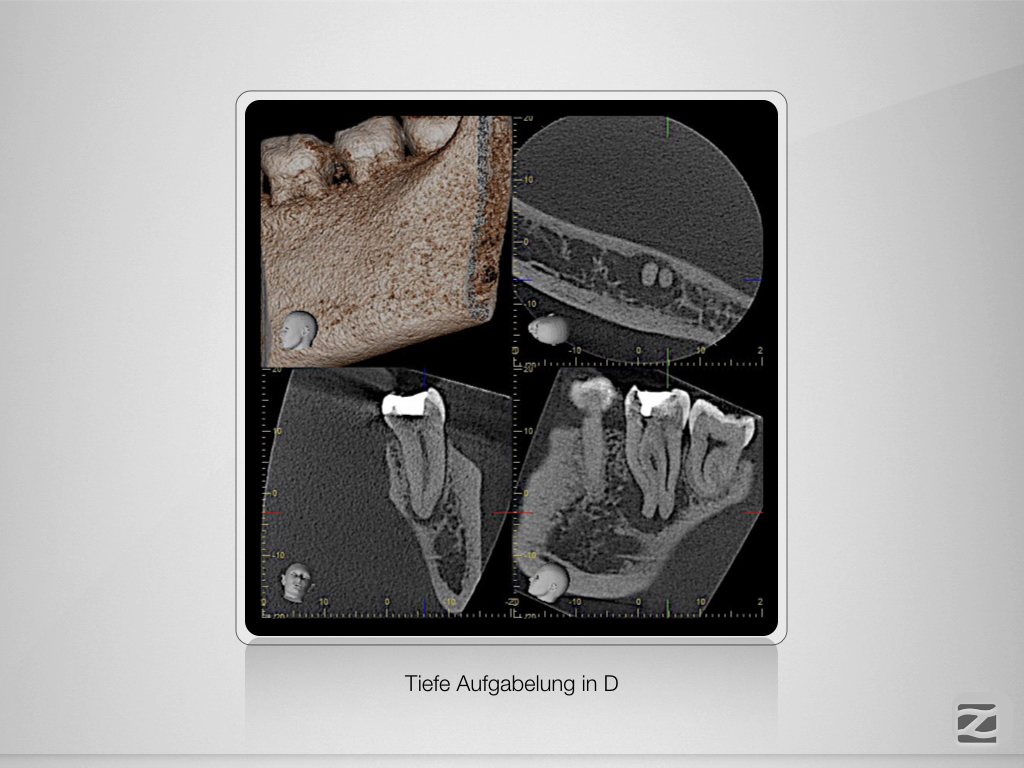

37D.004

Geometrische Herausforderung